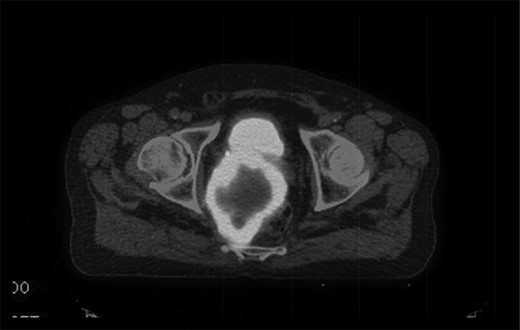

The multidisciplinary team review advised neoadjuvant treatment with imatinib mesylate and further reassessment. Repeat MR pelvis and staging PET CT abdomen, thorax and pelvis were then performed. These showed a large extra-luminal tumour with downsizing in tumour bulk (6 × 5.7 × 5.4 cm) (Figs 3–5) but in close approximation with the right seminal vesicle.

Axial fused PET-CT image pre-treatment, demonstrating that the mass has avid peripheral tracer uptake and a hypometabolic, tracer inavid centre.